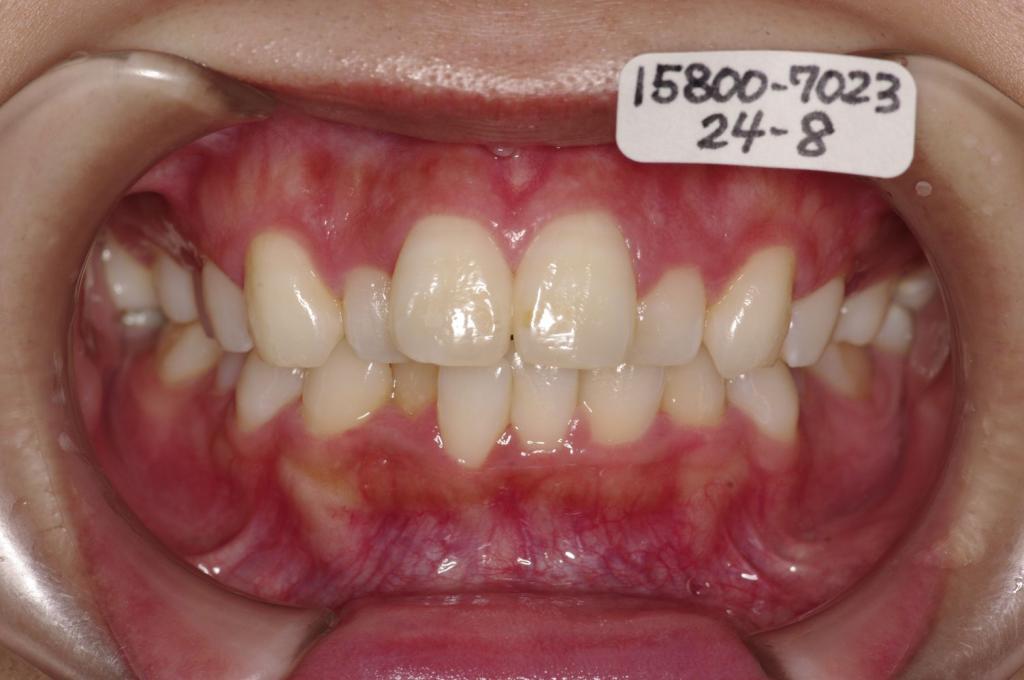

- 顎、顔の歪みの矯正治療

- 咬み合わせが悪い